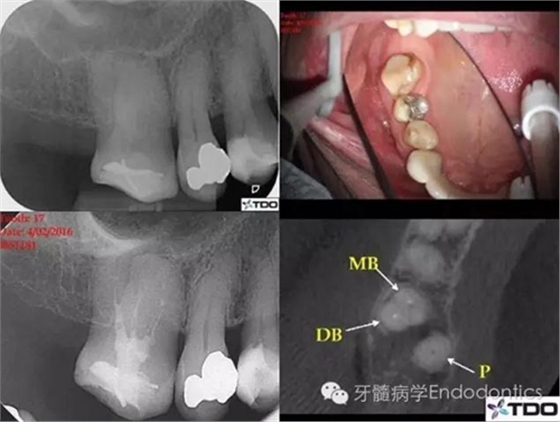

該上頜磨牙盡管位于第一磨牙的位置,但是解剖結(jié)構(gòu)類似第二磨牙。初診時(shí)醫(yī)生尋找到3個(gè)根管,近中頰根具有粗大、卵圓形的根管口,常見于具有融合根的上頜第二磨牙。醫(yī)生為確定近中頰根僅有一個(gè)根管,氫氧化鈣封藥后拍攝CBCT。CBCT上近頰根似乎只有一個(gè)居中的根管,醫(yī)生不確定MB根管是否在下段存在二分叉(圖1)。

二診充填根管后的X線片可看到MB根管上段粗大,下段突然變窄,糊劑進(jìn)入了可能存在的MB2(根尖二分叉)中(圖2)。

圖1

圖2